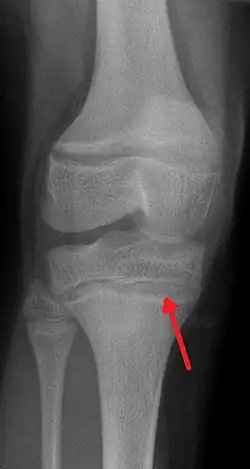

![]() | |

| An X-ray demonstrating the characteristic finding of lead poisoning in humans—dense metaphyseal lines. | |

Exposure to lead can occur through contaminated air, water, dust, food, or consumer products.[2] Lead poisoning poses a significantly increased risk to children and pets as they are far more likely to ingest lead indirectly by chewing on toys or other objects that are coated in lead paint.[2] Additionally, children absorb greater quantities of lead from ingested sources than adults. Exposure at work is a common cause of lead poisoning in adults, with certain occupations at particular risk.[7] Diagnosis is typically by measurement of the blood lead level.[2] The Centers for Disease Control and Prevention (US) has set the upper limit for blood lead for adults at 10 μg/dL (10 μg/100 g) and for children at 3.5 μg/dL;[8] before October 2021 the limit was 5 μg/dL.[9][10] Elevated lead may also be detected by changes in red blood cells or dense lines in the bones of children as seen on X-ray.[4]

Blood lead levels are an indicator mainly of recent or current lead exposure, not of total body burden.[210] Lead in bones can be measured noninvasively by X-ray fluorescence; this may be the best measure of cumulative exposure and total body burden.[40] However, this method is not widely available and is mainly used for research rather than routine diagnosis.[106] Another radiographic sign of elevated lead levels is the presence of radiodense lines called lead lines at the metaphysis in the long bones of growing children, especially around the knees.[211] These lead lines, caused by increased calcification due to disrupted metabolism in the growing bones, become wider as the duration of lead exposure increases.[211] X-rays may also reveal lead-containing foreign materials such as paint chips in the gastrointestinal tract.[29][211]